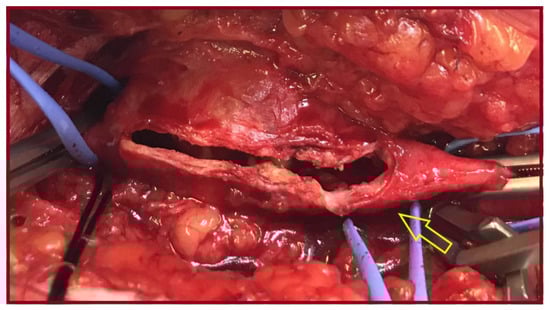

Simultaneous Endovascular Abdominal Aortic Aneurysm Repair and Open Repair of Common Femoral Artery Aneurysm: Short Case Series and Current Review

by Spyros Papadoulas, Melina Stathopoulou, Andreas Tsimpoukis, Chrysanthi Papageorgopoulou, Konstantinos Nikolakopoulos, Nikolaos Krinos, Aliki Skandali, Petros Zampakis, Petraq Mustaqe, Agron Dogjani, Francesk Mulita and Vasileios Leivaditis

J. Clin. Med. 2025, 14(22), 7988; https://doi.org/10.3390/jcm14227988 - 11 Nov 2025

Background: Common femoral artery aneurysms are rare and are usually associated with aneurysms at other sites, mainly the aorta, iliac, popliteal, superficial femoral, and profunda femoral artery. This combination poses the challenge of synchronous repair for clinically relevant aneurysms. Although endovascular abdominal aortic [...] Read more.

Background: Common femoral artery aneurysms are rare and are usually associated with aneurysms at other sites, mainly the aorta, iliac, popliteal, superficial femoral, and profunda femoral artery. This combination poses the challenge of synchronous repair for clinically relevant aneurysms. Although endovascular abdominal aortic aneurysm repair is the main type of treatment for abdominal aortic aneurysms nowadays, this is not true for common femoral aneurysms, where open repair remains the gold standard. These two distinct operations could be combined in a one-stage procedure when aortoiliac and common femoral aneurysms present simultaneously. This approach potentially saves time and costs, without increasing complications. Methods: A retrospective search was conducted in the Vascular Surgery Department database of a tertiary referral center for vascular surgery, covering procedures from January 2005 to May 2025. Patients were included if they had undergone simultaneous endovascular abdominal aortic aneurysm repair and open repair of a common femoral artery aneurysm. Clinical records, operative details, imaging studies, and follow-up data were reviewed. We additionally provide a literature review regarding this approach. This review additionally incorporates the current knowledge regarding the treatment of common femoral artery aneurysms. Results: Out of 668 endovascular abdominal aortic aneurysm repair procedures, three patients (0.45%) were identified. These three patients were among five patients who were treated for true common femoral artery aneurysm by open repair in the same time interval. All of the patients are currently in good condition without late complications. One patient, who had not performed any follow-up imaging, was diagnosed with large aneurysms at other sites, 10 years later. Conclusions: The combined one-stage endovascular abdominal aortic repair and open repair of a common femoral artery aneurysm by interposition grafting is technically a simple approach that led to satisfactory outcomes. Full article

(This article belongs to the Special Issue Current and Emerging Treatment Options for Aortic Aneurysms)